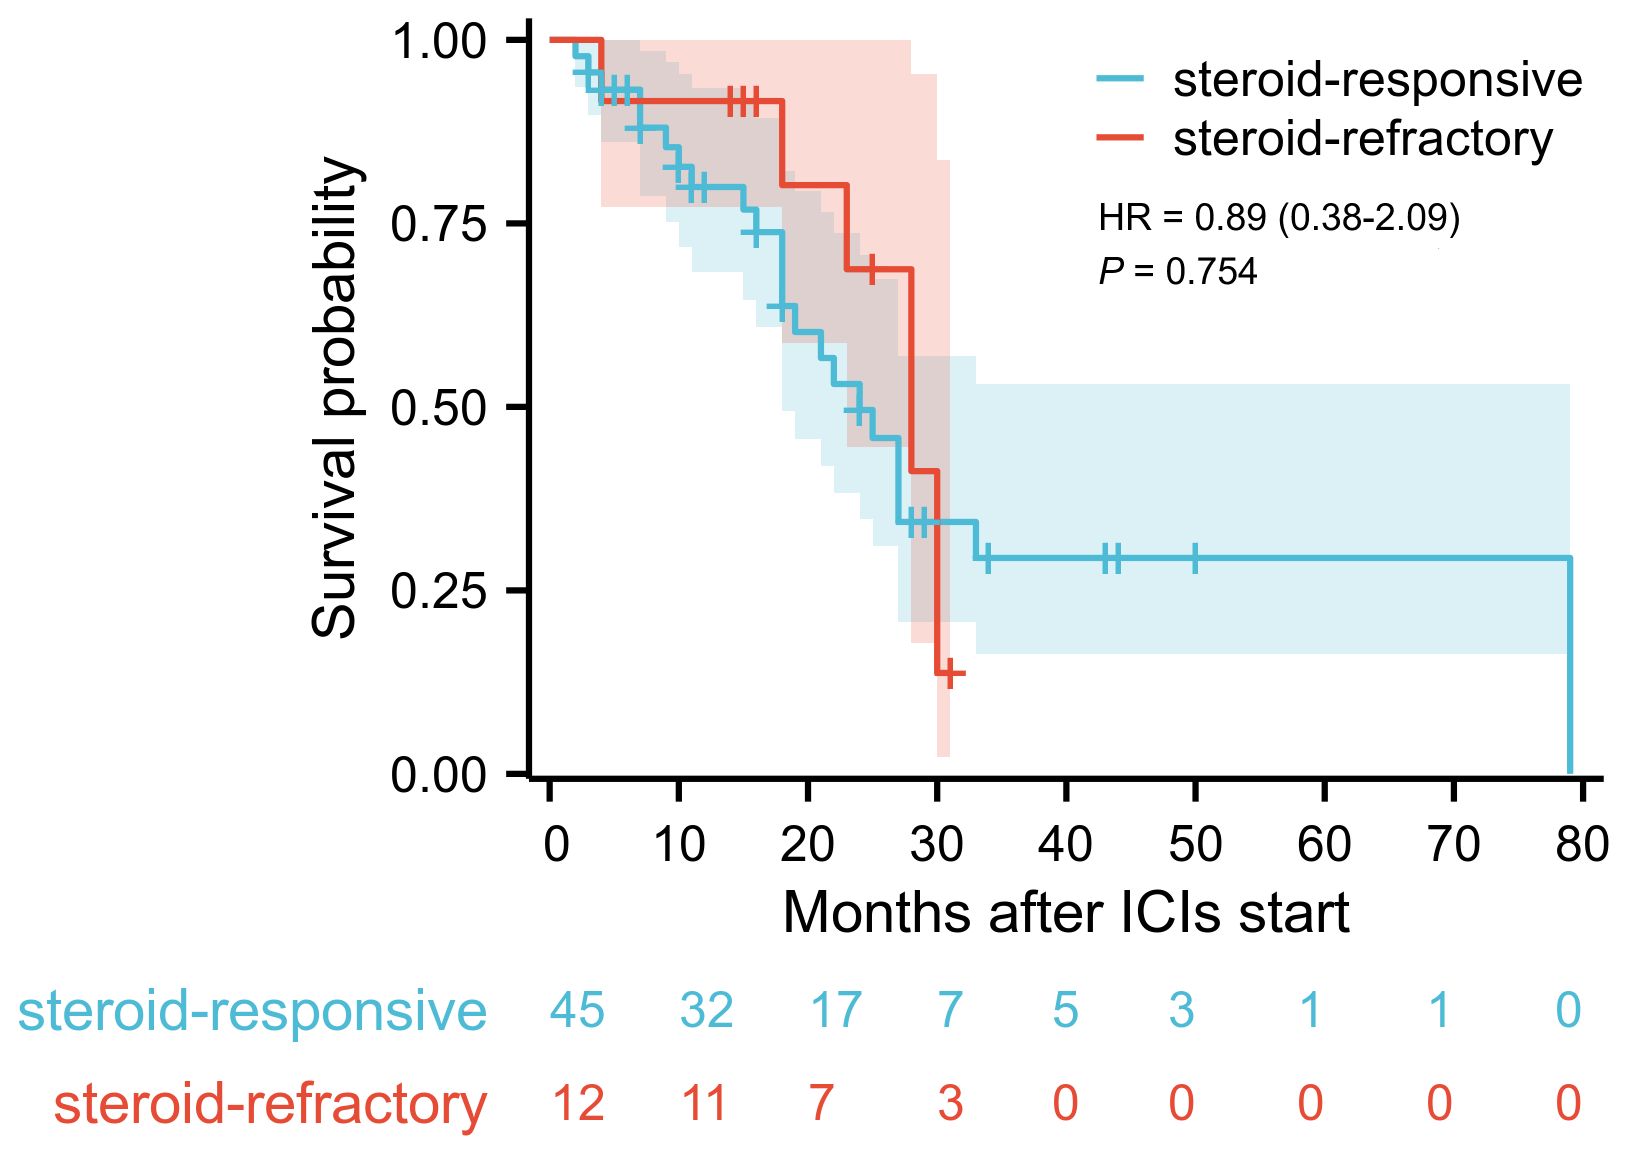

Results: A total of 57 patients were included, with 45 patients in the steroid-responsive group and 12 patients in the steroid-refractory group. Univariate analysis revealed differences between the two groups in the time to colitis onset (median days: 97 vs. 141, P = 0.037), presence of fever (4.4% vs. 25.0%, P = 0.045), presence of ulcerative lesions (26.9% vs. 34.6%, P = 0.036), grades of colitis (P = 0.011), and serum interleukin-6 (IL-6) level (24.1 ± 20.5 pg/mL vs. 81.7 ± 38.7 pg/mL, P < 0.001). Multivariate regression analysis indicated that serum IL-6 level was an independent risk factor for steroid-refractory. Kaplan-Meier survival analysis showed no significant difference in survival time between the two groups.

Multivariate logistic regression analysis was performed to identify risk factors associated with poor response to corticosteroid therapy. Univariate analysis indicated that longer time to onset of colitis (OR: 1.011, 95% CI: 1.001-1.022, P = 0.037), presence of fever (OR: 7.167, 95% CI: 1.042-49.279, P = 0.045), presence of ulcerative lesions (OR: 11.571, 95% CI: 1.172-114.262, P = 0.036), higher colitis grade (OR: 5.817, 95% CI: 1.505-22.476, P = 0.011), and elevated serum IL-6 level (OR: 1.062, 95% CI: 1.028-1.098, P < 0.001) was associated with poor response to corticosteroid therapy (Supplementary Table 1). Multivariate analysis revealed that elevated serum IL-6 level was an independent risk factor for poor response to corticosteroid therapy in patients with ICI-induced colitis (OR: 1.051, 95% CI: 1.005-1.100, P = 0.028) (Figure 3). During the study period, a total of 30 patients died, corresponding to an overall mortality rate of 52.6%. Among these deaths, 24 patients were attributed to tumor progression, 4 patients were due to cardiovascular disease, and 2 patients were due to pulmonary infection. Kaplan-Meier survival analysis revealed no significant difference in overall survival time between the steroid-responsive group (median 24.0 months, 95% CI: 19.3-28.7) and the steroid-refractory group (median 28.0 months, 95% CI: 21.7-34.3) (P = 0.754) (Figure 4).

Figure 4. Kaplan-Meier survival curve of overall survival in steroid-responsive group and steroid-refractory group. Blue curve demonstrates the overall survival for steroid-responsive group (n=45), red curve for steroid-refractory group (n=12). Log-rank test revealed no significant difference in survival time (P = 0.754).

For patients with steroid-refractory colitis, the use of SIT is currently established as the standard second-line treatment. However, the combined immunosuppressive effects of corticosteroids and SIT must be carefully considered in ICI-induced colitis patients due to potential toxicities, including serious infections such as Pneumocystis jirovecii pneumonia and infliximab-related hypersensitivity reactions (18, 19). Despite these risks, most studies investigating ICIs in advanced malignant tumors demonstrate no detrimental impact of SIT on cancer survival outcomes (20–22). Consistent with these findings, our study also showed no significant difference in survival time between patients treated solely with corticosteroids and those who received infliximab due to poor corticosteroid response during the follow-up period, as indicated by Kaplan-Meier survival analysis. It is important to recognize that survival in patients with malignancies is influenced by multiple factors, including tumor type, disease stage, underlying comorbidities, and responsiveness to anti-cancer therapies. Previous studies have shown that severe irAEs during ICI therapy and poor therapeutic responses to corticosteroids or infliximab may reflect heightened immune activation, potentially correlating with favorable tumor outcomes (23). Collectively, these observations imply that early escalation to SIT with agents like infliximab in steroid-refractory cases may not compromise survival outcomes. Instead, timely SIT implementation could shorten the disease course of ICI-induced colitis, thereby positively influencing quality of life and reducing disease burden.